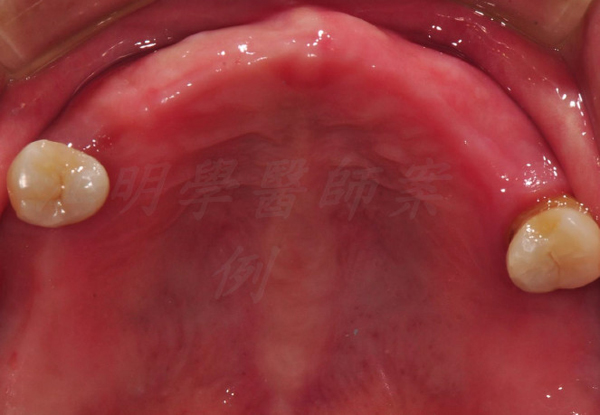

治療前